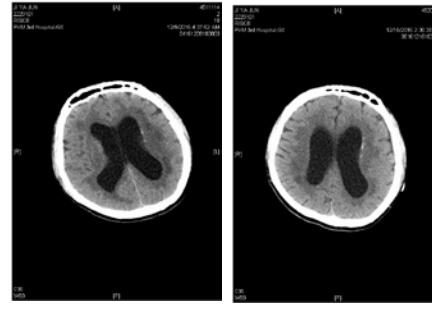

| 图 1 左侧为2016年12月8日我院颅脑CT,右侧为2016年12月15日我院复查颅脑CT,两次颅脑CT均提示双侧侧脑室扩张,无明显变化 |

患者,男,31岁,既往体健。因“间断发热、咳嗽10 d,昏迷16 h”于2016年12月9日入院。患者2016-11-30无诱因出现咳嗽、发热,抗感染治疗3 d后,症状好转。2016-12-6患者再次出现上述症状,最高体温38℃,伴头痛。2016-12-8 19:31于本院就诊期间出现意识模糊,瞻妄,次日02:15患者深昏迷,呼之不应。查体:体温38.5℃,脉搏131次/min,呼吸29次/min,血压126/56 mmHg(1 mmHg=0.133 kPa), 心、肺、腹未见异常。专科情况:深昏迷,双侧瞳孔不等大,左侧d=5.5 mm, 右侧d=6.0 mm, 双侧对光反射消失,疼痛刺激无反应,角膜反射未引出,脑神经查体不合作,四肢肌力查体不合作,双上肢肌张力高,双下肢肌张力正常,双侧膝、跟腱反射亢进,踝阵挛,颈强直,克氏征阳性、布氏征阳性。颅脑CT示双侧侧脑室低密度影,颅内感染?双侧侧脑室扩张。血常规:白细胞15.43×109/L,中性粒细胞百分比4.62%;降钙素原3.74 ng/mL, 12月9日行腰椎穿刺抽出淡黄色微混脑脊液,压力>300 cmH2O(1cmHg=0.098kPa), 脑脊液常规:细胞总数864 ×106/L,白细胞818×106/L,多核细胞80%,单核细胞20%,生化:氯113.3 mmol/L,葡萄糖1.00 mmol/L,总蛋白258.0 g/L,革兰染色、墨汁染色、抗酸染色阴性,脑脊液培养结果阴性。血培养结果示:肺炎链球菌。诊断为化脓性脑膜炎,病原菌为肺炎链球菌。给予降颅压,抗感染治疗后,症状好转,2016-12-12患者疼痛刺激有反应。2016-12-20神志转清,可按指令发出动作,但遗留有双侧动眼神经损伤,表现为双侧瞳孔散大,双侧对光反射消失,双侧眼睑下垂,左侧明显,双侧瞳孔各方位(除外展位外)运动不良;此外,合并双侧视神经、左侧面神经损伤,表现为无光感,左侧额纹消失,左侧鼻唇沟略浅。2016-12-26患者恢复部分光感,但视野缺损,无法分辨颜色。双侧动眼神经损伤及左侧面神经损伤未见明显改善,查体脑膜刺激征仍阳性。2016-12-15复查颅脑CT较前无明显变化。2016-12-27颅脑磁共振示脑积水,颅底感染,考虑患者动眼神经及其余脑神经损伤与高颅压压迫脑神经及颅底感染侵及脑神经有关,建议患者外院行脑室穿刺引流术进一步治疗。